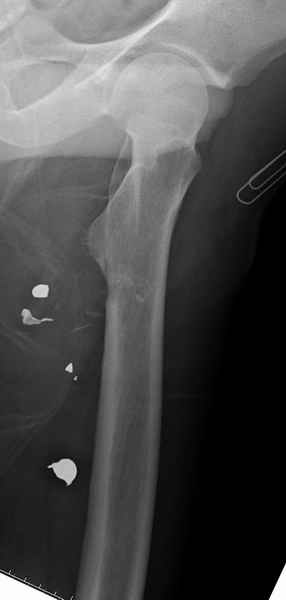

Больной с огнестрельным переломом бедра с вовлечением около 15% медиального кортекса, входное отверстие около 1 см в диаметре; стабильный, без сосудистых и неврологических признаков.

До развала Союза, более 15 лет работая ортопедом, встретил не более 4-5 случаев повреждения кости в результате огнестрельного ранения, и все они были бытовыми, т.е. случайными ранениями во время охоты, или муж в порыве ревности..

После развала Союза, когда мафиозные братья стали делить сферы влияния, огнестрельные ранения случались уже по одному-два в каждые 3-4 месяца, и более серьёзными скорострельными оружиями.

Наши приемные отделения (ER), как и во многих больших американских городах, за дежурство иногда обслуживают более 5 случаев огнестрельного ранения, а сколько из них не доходят до приемных отделении госпиталей никто не считает, так что в некоторых кварталах больших городов даже днем невозможно проехать без риска быть ограбленным или получения огнестрельного ранения, как в настоящей

войне.

Входные маленькие отверстия от ранении просто игнорируются, никаких дренажей, как любое колотое ранения, они закрываются и были случаи через месяц. Конечно, ведется профилактика открытых ранении: сыворотки и т.д., но еще самое главное уделяем профилактике образования перелома из-за стресса в результате дефекта кортикального слоя.

Литературные данные о влиянии кортикального дефекта на стрессовые переломы в длинных трубчатых костях в основном встречаются в онкологии, например кортикальный дефект более 50% имеет больше шанса стрессовых переломов, чем в нашем случае.

Это при нормальном обществе, когда больной понимает риск осложнении и следует врачебным рекомендациям, с пониманием относится к осложнениям, принимая вину на себя и без адвокатов...

Учитывая, что больной получил травму не во время визита в церковь, и он является одним из представителем 40 миллионного “outstanding itizen”, без медицинской страховки, без работы в свои 39 лет, и без надлежающей ортопедической дисциплины у которого отсутсвует страх стрессового перелома, было рекомендовано оперативное лечение: профилактическое антеградное интрамедуллярное штифтование.